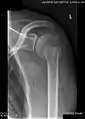

| The glenoid labrum, labeled glenoid ligament, is damaged in a Bankart lesion. Lateral view demonstrating the articular surface of the right scapula is shown. | |